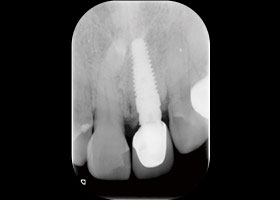

假牙拆除前的X光片,可看出假牙已不密合。

假牙拆除後,因續發性齲齒已深至牙肉下,且牙根明顯鬆動,遂無法保留牙根。